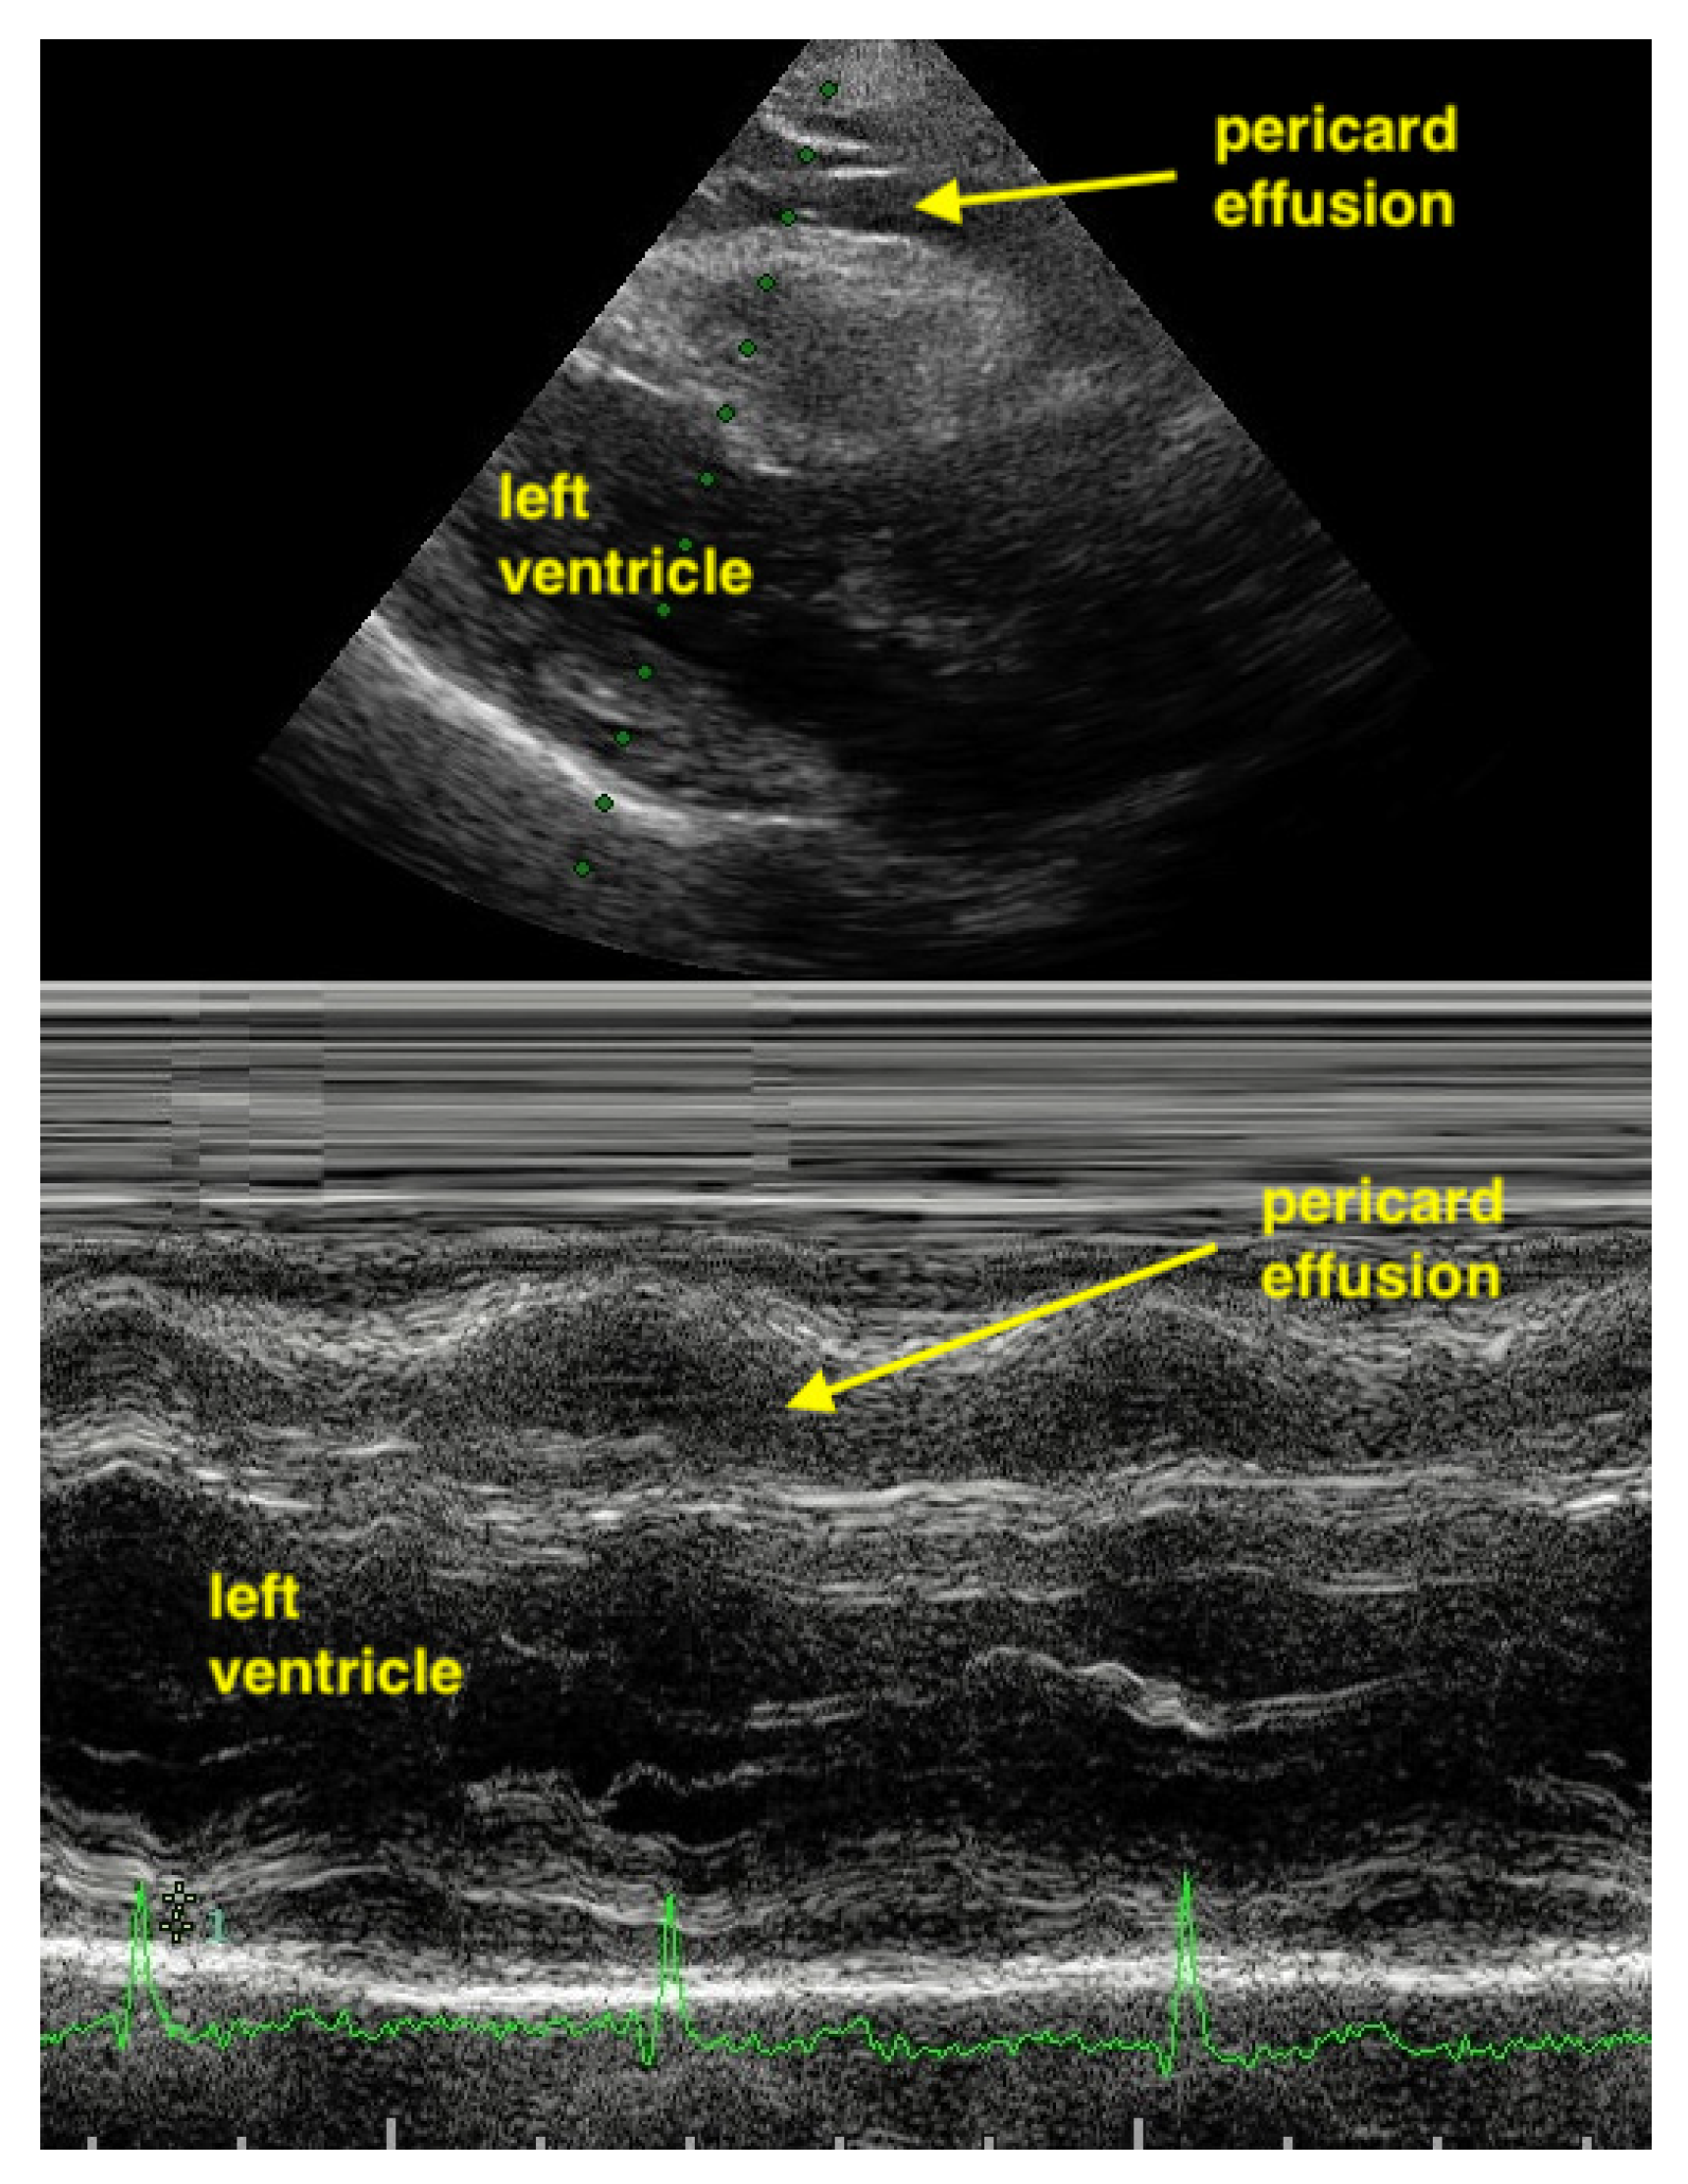

M-Mode can help to differentiate between pericardial effusion and fat. Pericardial effusion undergoes a fluctuation during heart movement and so shows a hypoechoic band which moves in thickness. In contrast, the hypoechoic band of fat does not change in thickness (Figure 11 and Figure 12).

Figure 11.

In the apical 4CV (Chambers almost not to see), in the apex is a broad hypoechoic band which has always the same size. 4CV = Four Chamber view.

Figure 12.

In the parasternal long-axis view, the hypoechoic band of the pericardial effusion varying in size during heart contraction (undulating).